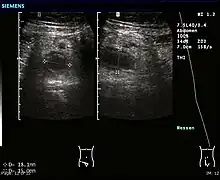

Ultrasound

Abdominal ultrasonography, preferably with doppler sonography, is useful to detect appendicitis, especially in children. Ultrasound can show the free fluid collection in the right iliac fossa, along with a visible appendix with increased blood flow when using color Doppler, and noncompressibility of the appendix, as it is essentially walled-off abscess. Other secondary sonographic signs of acute appendicitis include the presence of echogenic mesenteric fat surrounding the appendix and the acoustic shadowing of an appendicolith.[55] In some cases (approximately 5%),[56] ultrasonography of the iliac fossa does not reveal any abnormalities despite the presence of appendicitis. This false-negative finding is especially true of early appendicitis before the appendix has become significantly distended. Also, false-negative findings are more common in adults where larger amounts of fat and bowel gas make visualizing the appendix technically difficult. Despite these limitations, sonographic imaging with experienced hands can often distinguish between appendicitis and other diseases with similar symptoms. Some of these conditions include inflammation of lymph nodes near the appendix or pain originating from other pelvic organs such as the ovaries or Fallopian tubes. Ultrasounds may be either done by the radiology department or by the emergency physician.[57]